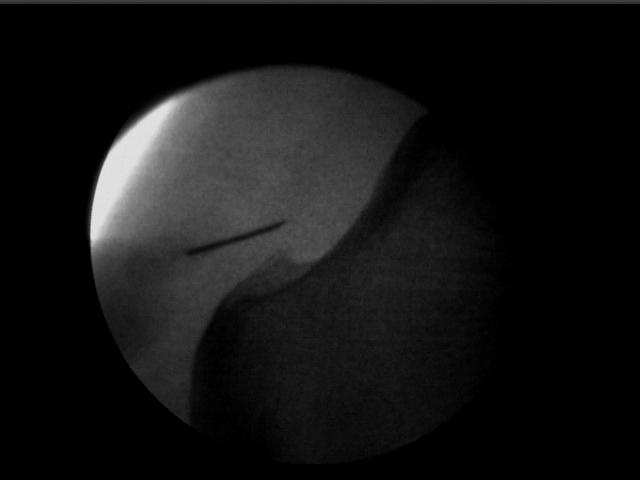

- Infiltración en Fascia Plantar